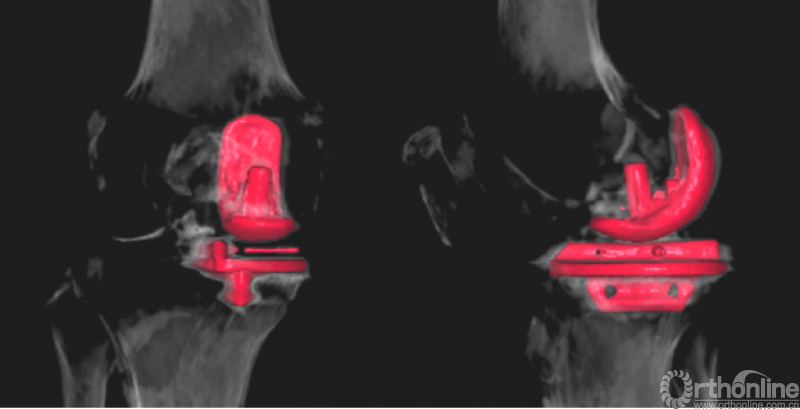

结果表明FAMA线与Akagi线基本平行,其夹角为4.272±0.552°。胫骨截骨块和胫骨假体的AP、ML长度无显著差异(AP差值0.007±0.154cm,p=0.674,ML差值0.020±0.195cm,p=0.155)。两组间的AP、ML长度无显著差异(AP:p=0.281,0.741,0.672,0.849,0.287;ML:p=0.3,0.866,0.085,0.255,0.09;假体型号由AA至D)。两组间的ML/AP比值无显著差异(p=0.141,0.646,0.255,0.607,0.384;假体型号由AA至D)。两组胫骨假体的内外侧位置(组1:0.87±0.03,组2:0.86±0.03,p=0.156)和外旋角度(组1:6.88±2.08°,组2:6.68±2.22°,p=0.746)无显著差异。

FAMA线基本平行于Akagi线,使用FAMA线进行胫骨垂直截骨,能实现胫骨假体的良好覆盖和正确旋转。此外,FAMA线通过FAM和ACL止点进行定位,两个解剖标志都能在术中直视下观察,相较于牛津UKA手术技术手册的方法更直观,也更利于外科医生学习并提高UKA技术。